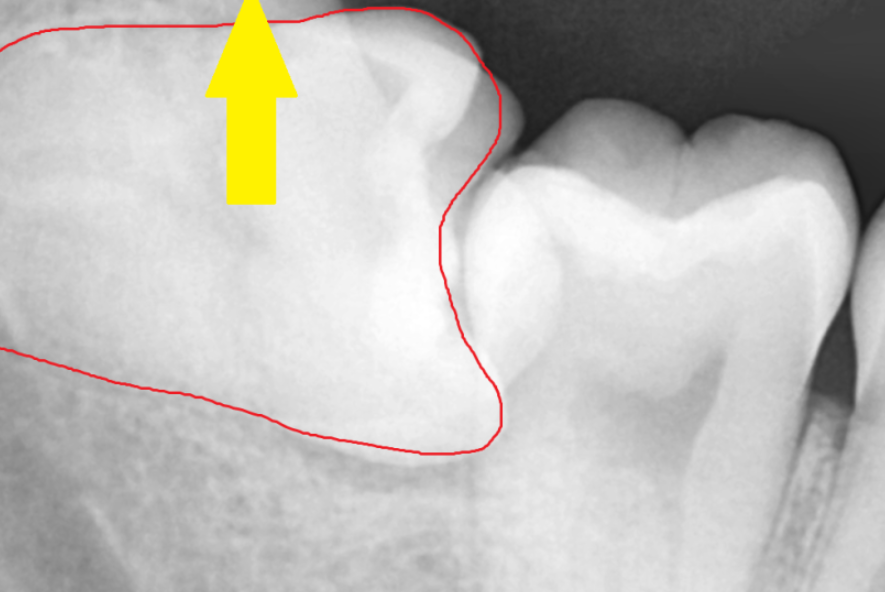

이렇게 누워서 난 사랑니는

수직으로 뽑을 수가 없기 때문에

쪼개서 뽑아야합니다.

발치 난이도도 올라가고

뼈도 삭제해야해서

발치 후 통증이 심할 수 있습니다.

해부학적으로 하치조 신경관과 근접하기 때문에

뽑고 나서 신경 손상 가능성도 있고요